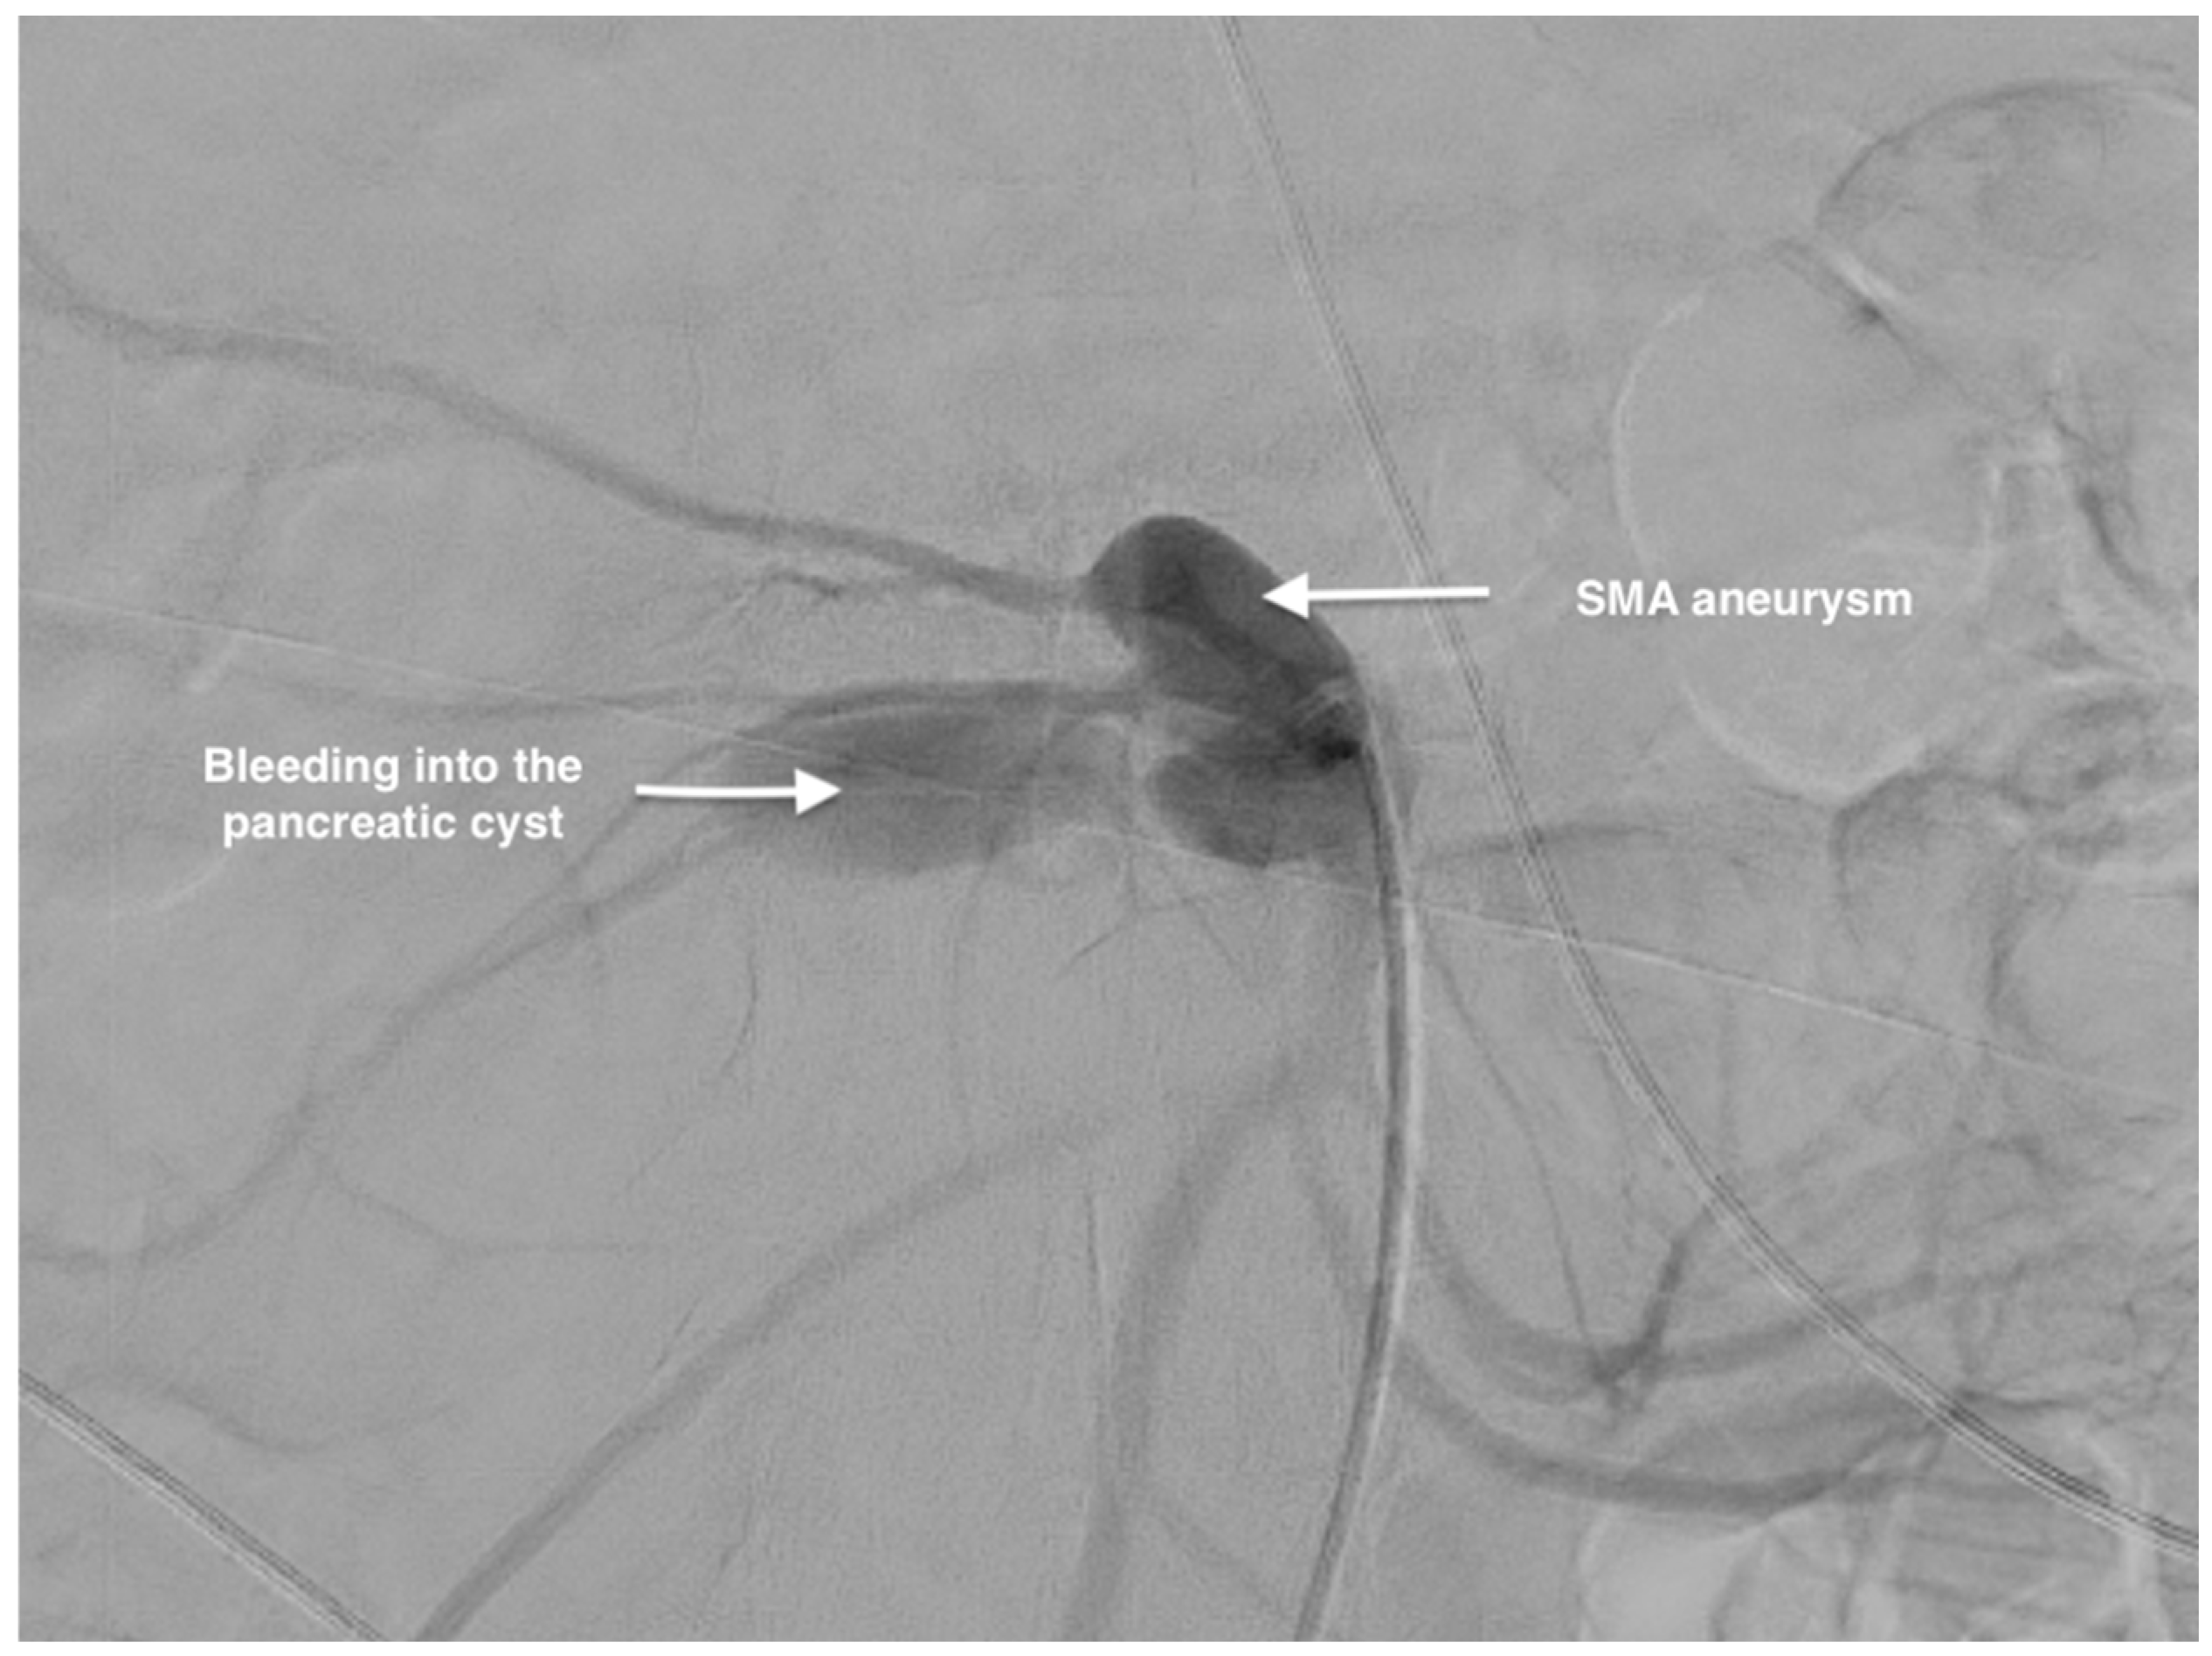

2. Case Report